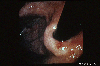

A case of a metastatic gastric tumor originating from breast carcinoma.

Endoscopy